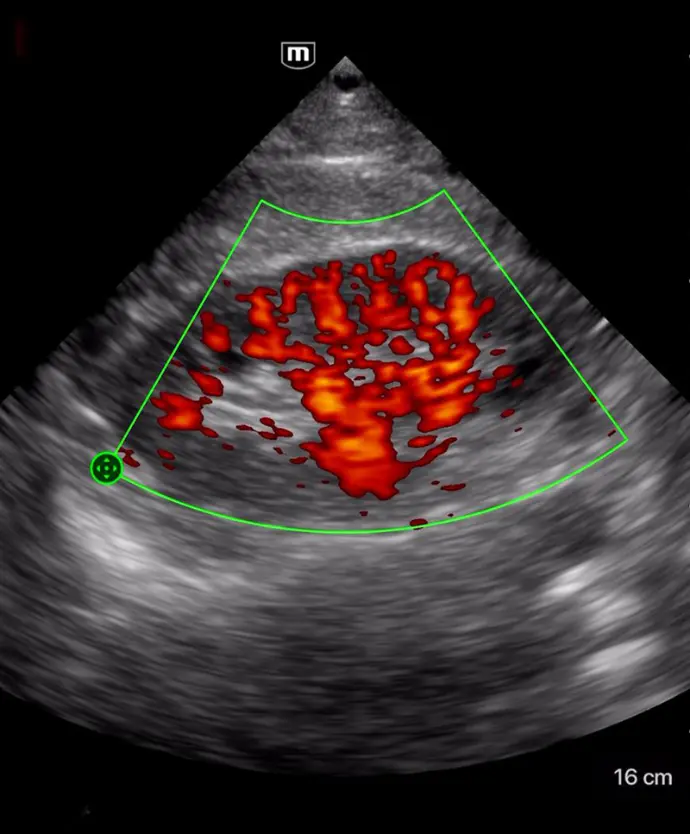

Различни режими на визуализация: B-mode, M-mode, Color Doppler, Power Doppler, PW Doppler

B-режим, М-режим, цветен доплер, Power доплер и PW доплер

Множество режими на визуализация

Бърза диагностика на сърдечната функция; скрининг за сърдечна патология

Клинични снимки